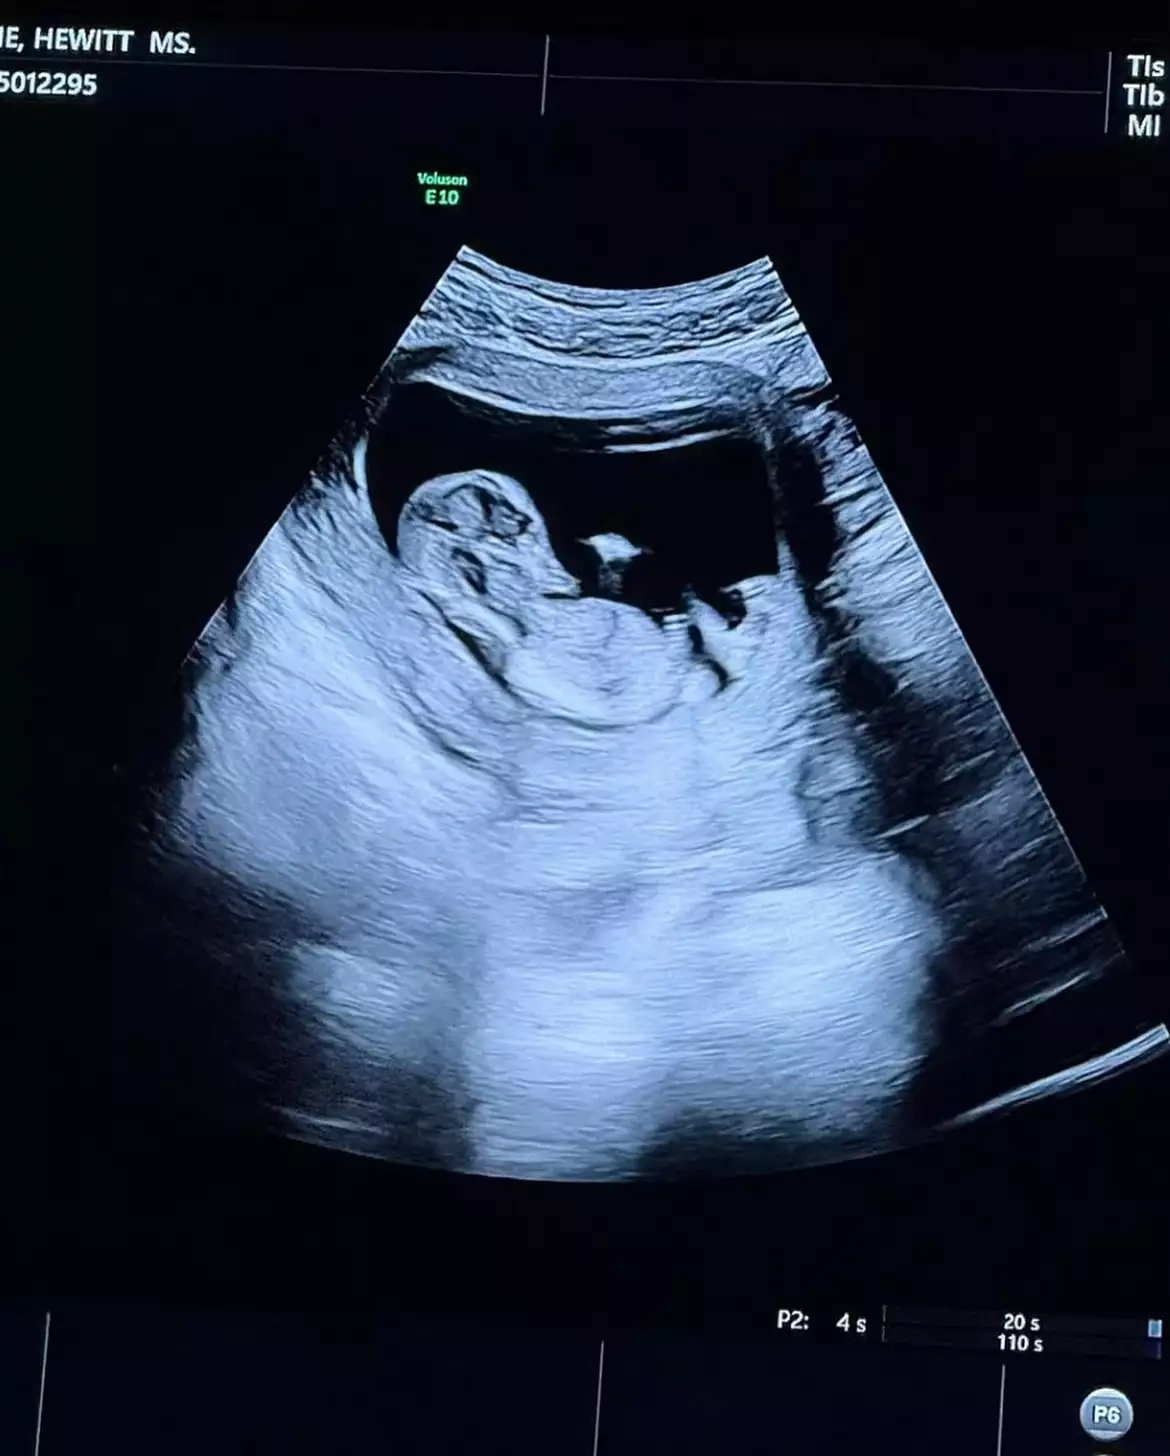

O, instaqramda körpənin ultrasəs görüntüsünü yayımlayaraq zarafatla belə yazıb: “Nəysə... indi hər kəs bizim sekslə məşğul olduğumuzu bilir.”